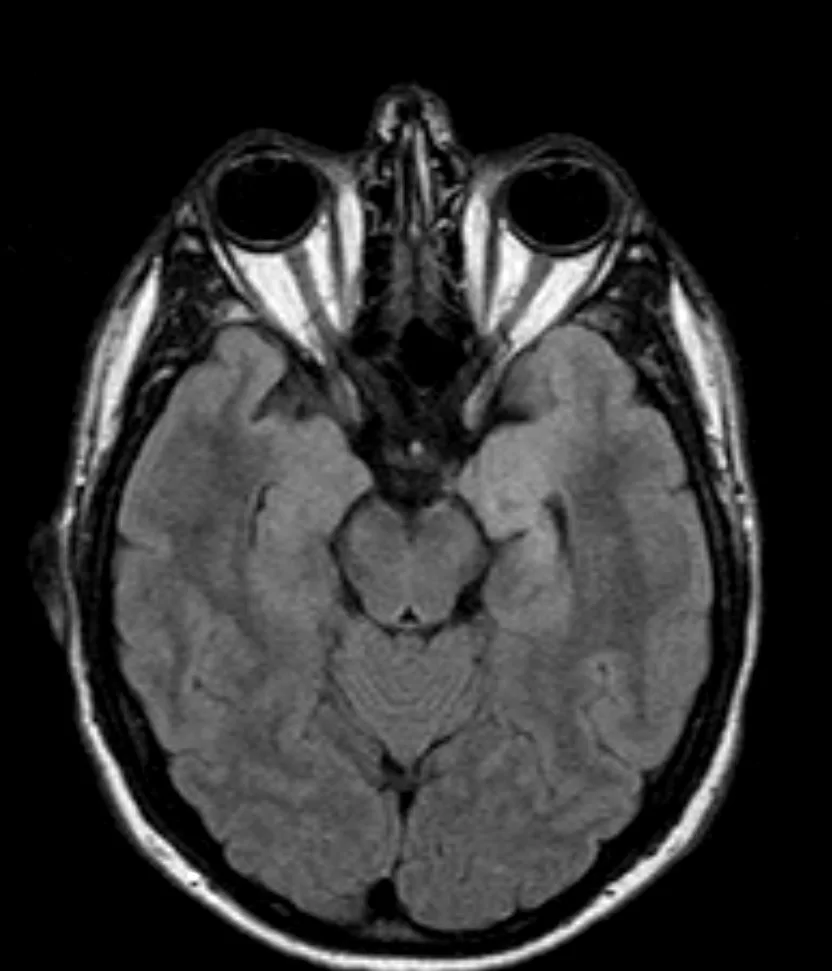

Γαγγλιογλοίωμα Ιπποκάμπου αριστερά

Ασθενής άνδρας, 38 ετών με πολλαπλά λιποθυμικά επεισόδια μετά από οσφρητική αύρα (επιληπτικές κρίσεις). Ο απεικονιστικός έλεγχος με μαγνητική τομογραφία